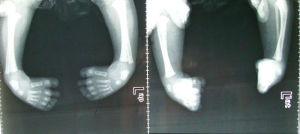

杵狀足杵狀足是下肢最常見的先天畸型,在東方民族的發生率約為十萬分之五。其中大約只有10%有家族史,其餘的可能是突變或子宮內環境影響所產生。男性發病率較高,約為女性的二倍,而罹患者其子女有10%會有此病。兩腳發病機率相似,約有一半病人為兩腳同時發病。臨床可見畸形的足向內下扭曲變形,整隻腳看起來像一個杵。這種畸形包括四個不同的部位:(一)足弓過高(空凹足)(二)前足內收變形(三)內翻變形(四)馬蹄足。

保守治療:首先要依序矯正四個畸形,接著要維持矯正後的正常位置至沒有再發的危險為止。嬰兒出生後便應開始接受治療,部分醫院採用的治療方法為Dr.Ponseti的系列石膏矯正法(Serialcasting)。先矯正足弓過高、前足內收,接著足跟內翻,最後才矯正馬蹄足。通常一至二星期需換一次石膏。大約五次的石膏以後,視需要作跟腱放鬆術;去掉石膏後,仍要每天作足部伸展運動並用足外轉支架固定(70度外轉,15度背屈)。支架的使用方式為全天使用二至三個月,之後晚上使用二到四年。

雖然此種治療的方法效果很好,對單純的杵狀足有九成以上的成功率,但仍有若干的病人需使用手術方式才能徹底矯正。目前多數骨科是採用關節及軟組織完全放鬆手術來治療這種抗拒性杵形足,大多選在六個月至一歲之間作手術。要有良好成績則最晚在三歲以前作此種手術。手術矯正後,同樣要上石膏,大約兩週時更換石膏並拆除縫合線,之後繼續石膏六週,以保持矯正結果。如果病人年齡超過六、七歲,只作軟組織放鬆術是不夠的,需加作切骨術。若超過十二歲,就必須作足關節固定手術。